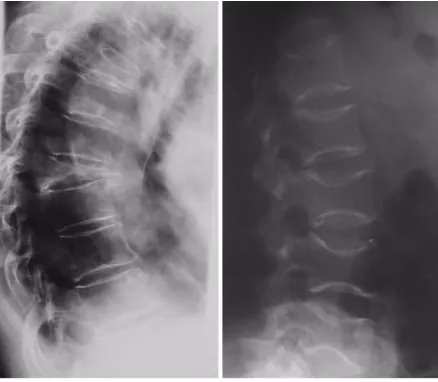

10. Scădere în înălțime sau suspiciune de fracturi vertebrale

O pierdere de înălțime de peste 4 cm față de înălțimea maximă din tinerețe, sau de 2 cm într-un interval scurt de urmărire (aproximativ 3 ani), este un semnal clinic care nu trebuie ignorat. Poate indica tasări vertebrale, uneori asimptomatice. Ghidurile recomandă ca aceste situații să ducă la evaluare imagistică vertebrală și la osteodensitometrie. DEXA, în combinație cu evaluarea morfometrică vertebrală (VFA) disponibilă pe platformele moderne, poate oferi o imagine completă a fragilității osoase.